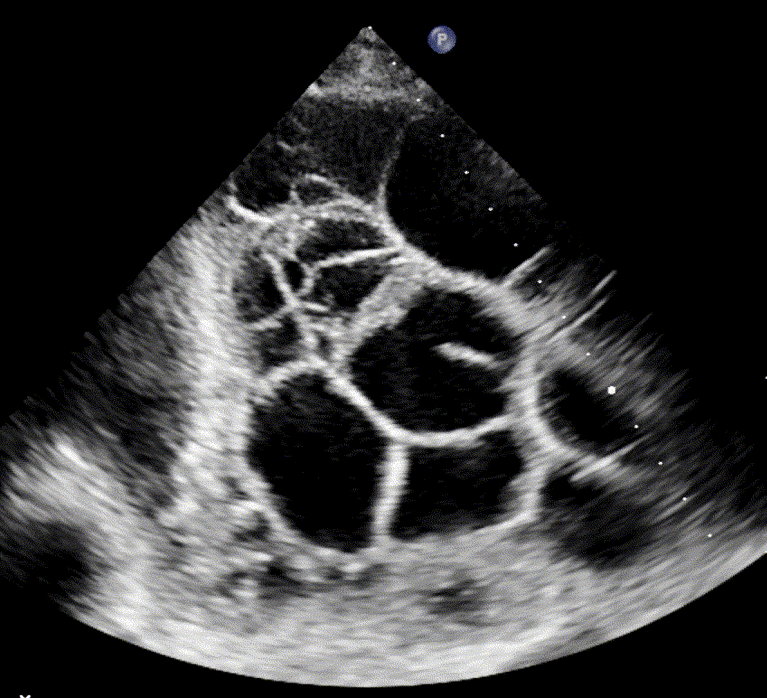

Loculated/Septated Pleural Effusion

Loculated pleural effusions, also referred to as septated effusions, are typically associated with exudative pleural processes. The term describes effusions in which the pleural fluid is divided into multiple compartments or “pockets” by fibrous septa.

These loculations arise from inflammatory or infectious processes, such as empyema, abscess formation, scarring, or fibrosis in the pleural cavity, which interfere with normal fluid movement and drainage within the pleural cavity.

Septated effusion in empyema